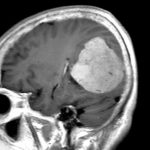

'23年12月

50代

脳腫瘍

頭蓋内腫瘍摘出術

No.’23_128 手術前1